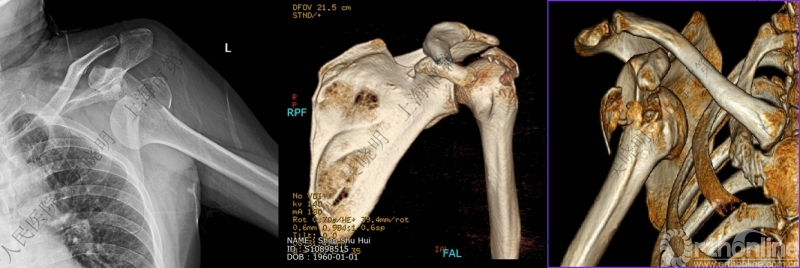

本组医源性骨折患者的影像学特点

均伴有大结节骨折;

可伴有外科颈骨折;

肱骨头可内移至喙突下;

肱骨头外翻畸形。

肩关节前脱位伴大结节骨折创伤机制2:肩胛盂与肱骨头撞击

老年性肩关节脱位伴大结节骨折:与肩胛盂和肱骨头撞击有关

骨折线可以延伸到肱骨头